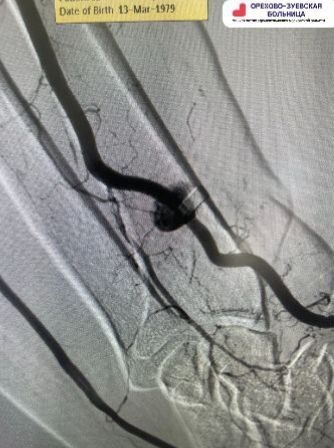

Врачи Орехово-Зуевской больницы спасли руку пациента от ампутации

В Орехово-Зуевскую больницу доставили 48-летнего мужчину с тяжёлой травмой: во время производственных работ металлическая стружка попала ему в руку и пробила доминантный сосуд, вызвав сильное кровотечение. Из-за маленьких размеров осколка его не удалось обнаружить обычным способом. Врачи приняли решение о проведении гибридной операции в рентгеноперационной под контролем ангиографа. С помощью высокоточного оборудования хирурги нашли и удалили осколок. «Повреждённый участок сосуда был восстановлен с помощью стент-графта – эндопротеза, который обеспечил герметичное закрытие дефекта и нормализацию кровотока», - рассказал заведующий региональным сосудистым центром, врач эндоваскулярной хирургии Дмитрий Тютьнев. Операция прошла успешно. Пациент чувствует себя стабильно, функции руки полностью сохранены.